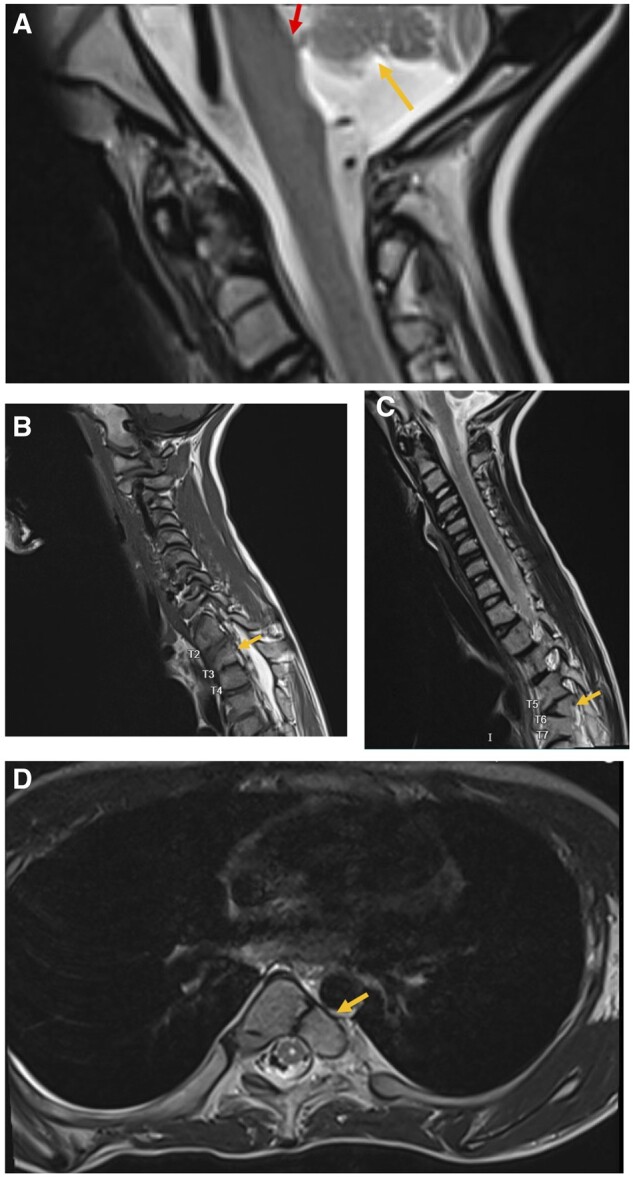

This case report highlights vertebral segmental anomalies and the fact that the child presented has a rare neurologic condition called pontine tegmental cap dysplasia. Additionally, this case aims to educate learners in developing a differential diagnosis for vertebral and cardiac anomalies such as VACTERL syndromes and common syndromes associated with butterfly vertebrae in children and adolescents.